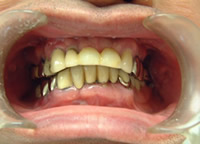

治療前

1.下11本、上1本抜歯、同時に総義歯セット

2.総義歯セット 正面口腔内

3.総義歯の入った正面観